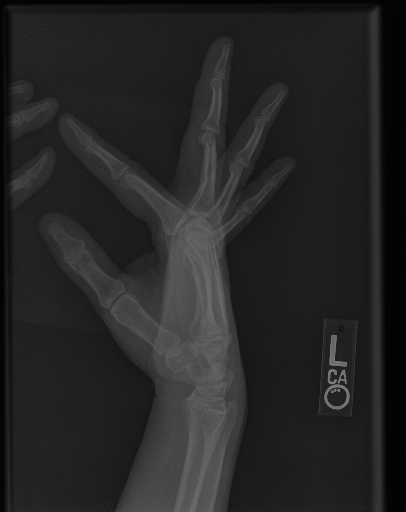

The first step in our pipeline is to detect the X-ray image carrier in the image. To this end, we apply OpenCV’s contour detection using Otsu binarization [14], and retrieve the minimum size bounding box, which does not need to be axis-aligned. This works sufficiently well as long as the majority of the image carrier is within the image (cf. Figure 3). However, the approach might fail for heavily tilted images or those where larger parts of the image carrier reach beyond the image border.

To further improve the detection of hands, and in particular split the images where two hands are depicted on one image, we manually labeled approximately 150 bounding boxes in the images. Using this small dataset, we fine-tune a pre-trained single shot multibox detector (SSD) [12] with MobileNet as taken from TensorFlow. An exemplary results can be seen in Figure 3.